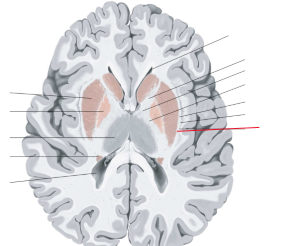

nucleus caudatus

putamen

globus pallidus

capsula interna (corona radiata)

capsula externa

capsula extrema

hippocampus

amygdala

fornix

laterale ventrikels (I en II)